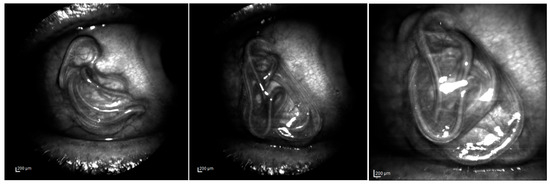

3.1. Morphology